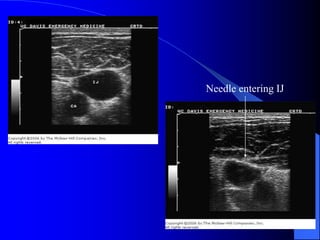

Internal Jugular Approach

 Positioning

– Right side preferred

– Trendelenburg position

– Head turned slightly away from side of venipuncture

 Needle placement: Central approach

– Locate the triangle formed by the clavicle and the sternal and

clavicular heads of the SCM muscle

– Gently place three fingers of left hand on carotid artery

– Place needle at 30 to 40 degrees to the skin, lateral to the carotid

artery

– Aim toward the ipsilateral nipple under the medial border of the

lateral head of the SCM muscle

– Vein should be 1-1.5 cm deep, avoid deep probing in the neck

Ultrasound-Guided Central

Venous Access

 Becoming standard of care

 Vein is compressible

 Vein is not always larger

 Vein is accessed under direct

visualization

 Helpful in patients with

difficult anatomy

Needle entering IJ